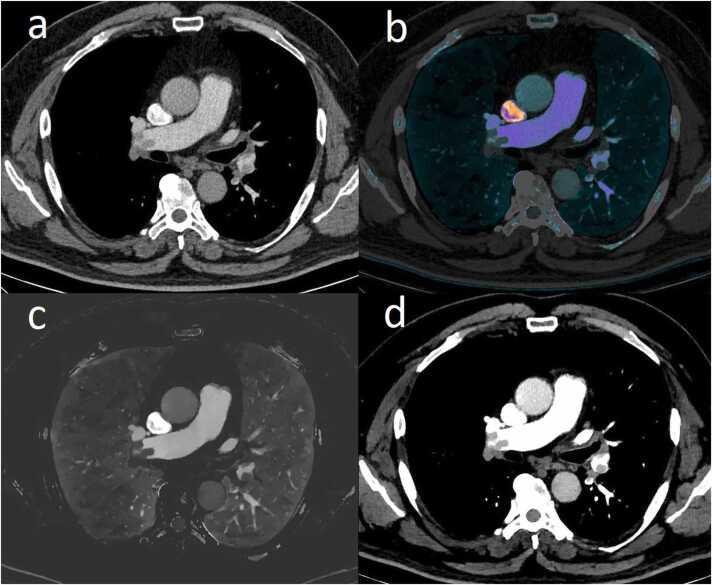

Roles of spectral dual-layer CT, D-dimer concentration, and COVID-19 pneumonia in diagnosis of pulmonary embolism.

To demonstrate advantages of spectral dual-layer computed tomography (CT) in diagnosing pulmonary embolism (PE). To compare D-dimer values in patients with PE and concomitant COVID-19 pneumonia to those in patients without PE and COVID-19 pneumonia. To compare D-dimer values in cases of minor versus extensive PE.

Prevalence of inconclusive PE findings differed significantly between CTS and CTC (0.8 % vs. 5.4 %, < 0.001). In all groups, D-dimer levels were significantly higher in PE positive patients than in patients without PE (CTC, 8.04 vs. 3.05 mg/L; CTS, 6.92 vs. 2.57 mg/L; COV, 10.26 vs. 2.72 mg/L, < 0.001). There were also statistically significant differences in D-dimer values between minor and extensive PE in the groups negative for COVID-19 (CTC, 5.16 vs. 8.98 mg/L; CTS 3.52 vs. 9.27 mg/L, < 0.001). The lowest recorded D-dimer value for proven PE in patients with COVID-19 pneumonia was 1.19 mg/L.

CTPAs using spectral dual-layer CT reduce the number of inconclusive PE findings. Plasma D-dimer concentration increases with extent of PE. Cut-off value of D-dimer with 100 % sensitivity for patients with COVID-19 pneumonia could be doubled to 1.0 mg/L. This threshold would have saved 110 (22 %) examinations in our cohort.